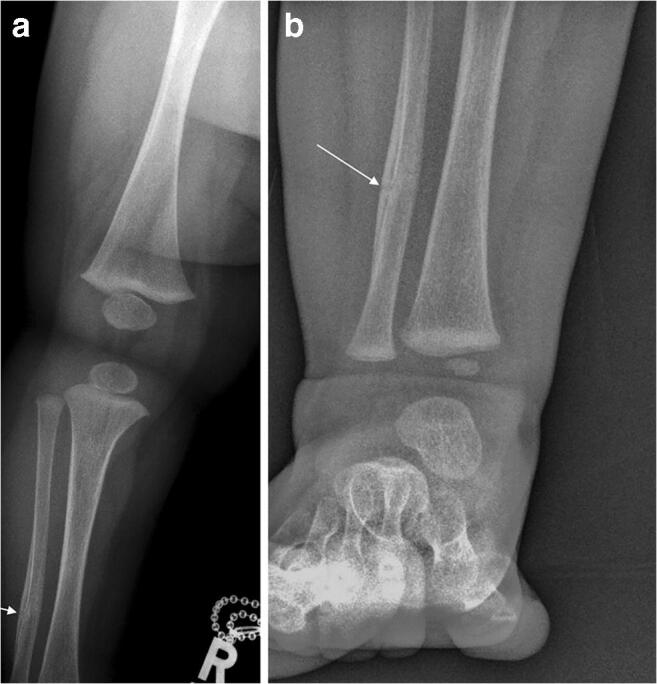

Fig. 3.

Right leg (a) and ankle (b) anteroposterior projections taken as part of the initial skeletal survey, 3 days after the images in Fig. 1 and a day after that in Fig. 2. There is a healing undisplaced fracture of the right fibular shaft at the junction of middle and distal thirds (arrows), i.e. at an almost identical location as the fracture of the left fibula seen in Figs. 1 and 2